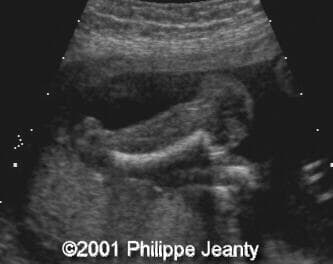

This fetus has a small amount of bowing and shortening of the right leg (compare to the left leg on the second image):

image19

image20